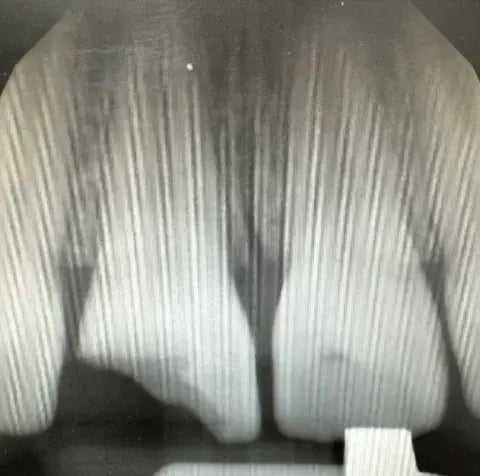

Coming out of school and residency, I was taught and practiced restoring these cases “free hand.” While I had no problem achieving the result I wanted, I’m sure all dentists can relate to how time-consuming Class IV’s can be. While other products and techniques exist with varying cost and complexity, I find that the best way to predictably, effectively and efficiently treat is with strip crowns.

As a pediatric dentist, I routinely place strip crowns on primary incisors. Through repetition, I naturally improved my esthetic skills and results over time. For any general dentist reading who may not be as familiar, it basically involves filling uncured restorative material into a tooth-shaped plastic mold, placing and curing it onto the tooth, and then removing the mold to leave behind a cured restoration. While for carious primary teeth we typically prefer glass ionomer for strip crowns (in vogue among pediatric dentists), for adult teeth we certainly prefer composite for its superior physical properties.

To break it down step-by-step, the technique involves:

- Bevel/etch/bond (business as usual)

a. (Tip: Etch for a full 30 seconds. Surface area is your friend for retention) - “Free hand” a small layer of OMNICHROMA BLOCKER to restore general shape

- Choose the correct size strip crown (my preferred brand for pediatrics and adults is Nowak) and trim to incisogingival length with scissors

- Fill the strip crown with OMNICHROMA Flow BULK

a. (Tip: pack starting from the incisal edge to prevent voids)

- Cure both sides

- Use a scaler to flick off the cured excess

- Remove (or strip–hence the name) the plastic mold off with an explorer

- Cure one more time for good luck

- If necessary, adjust occlusion and use a fine finishing bur or finishing strips to polish

That’s it, you’re done. Better and faster. The average treatment time is less than 10 minutes. You’ll usually find the margins seamless and the finishing flawless. I also find that because the restoration is basically full coverage, the retention is a lot stronger than free hand.